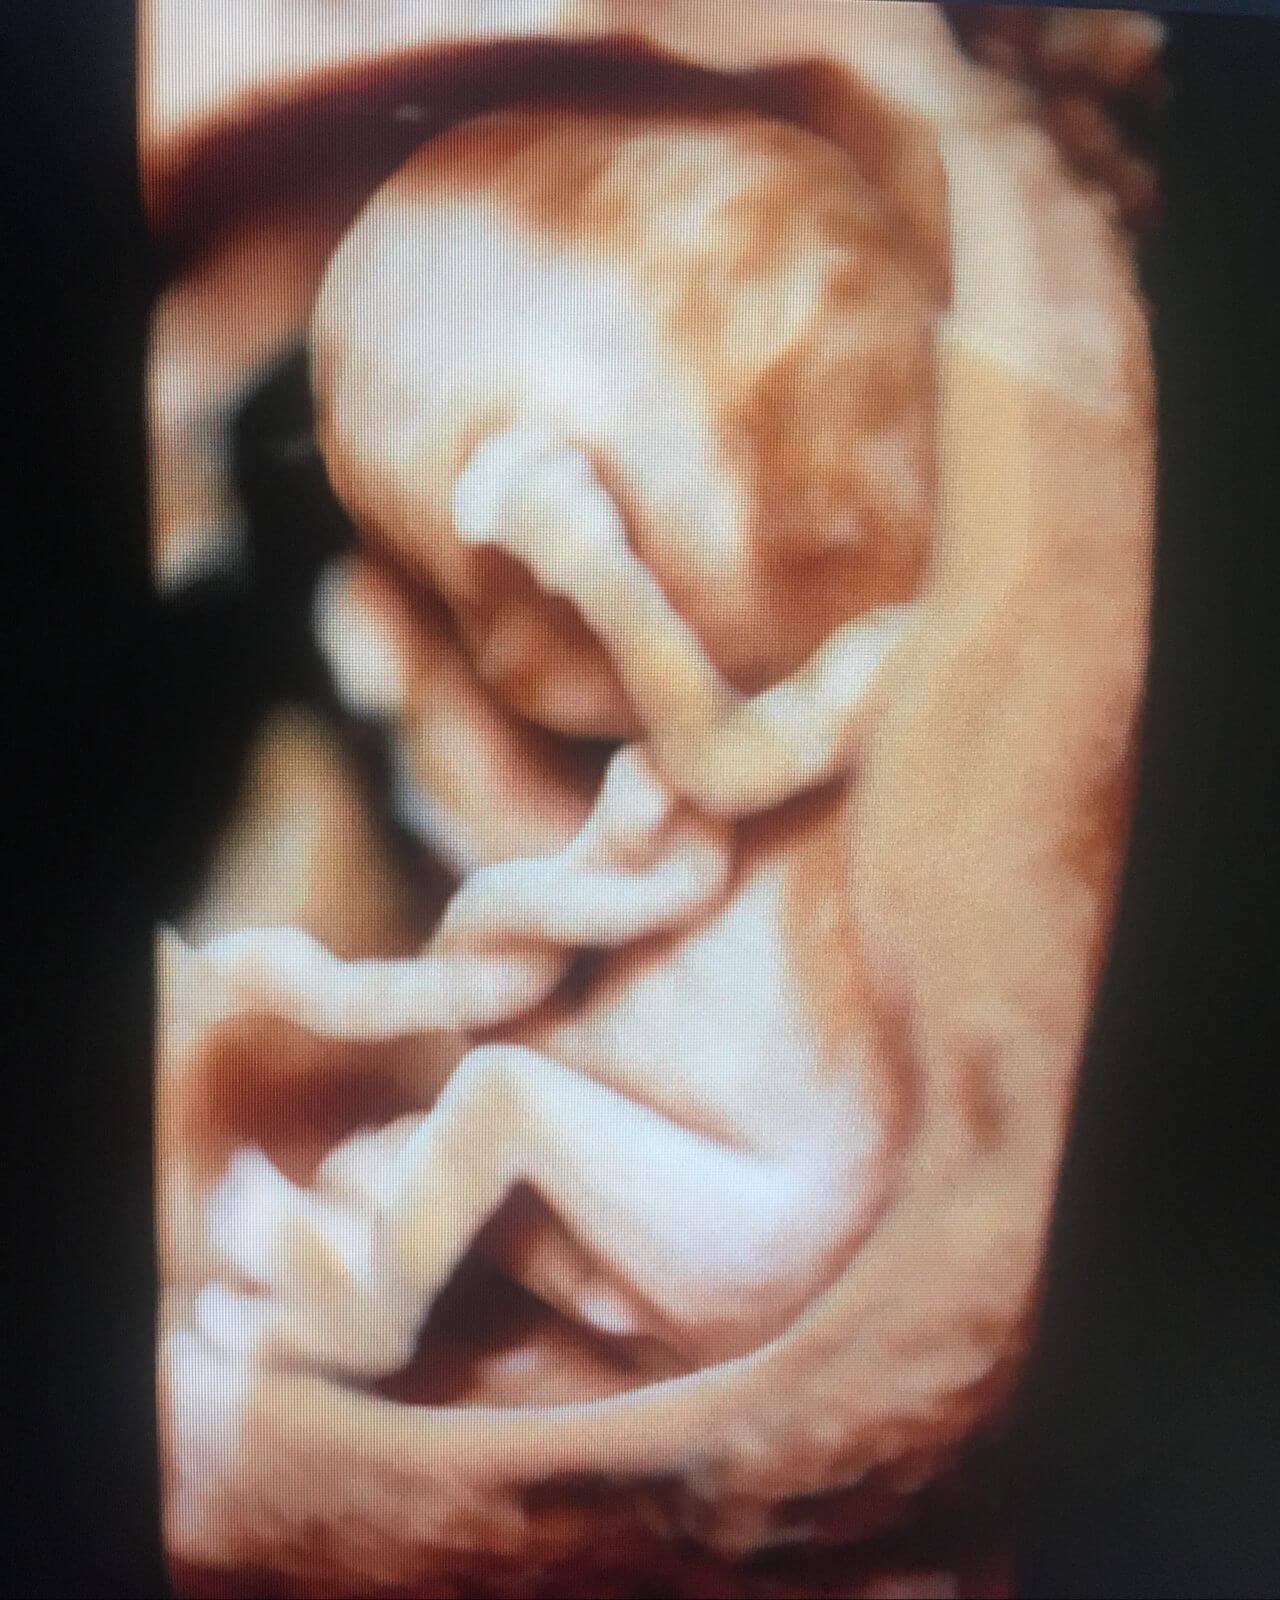

Realiza tamizaje de Síndrome de Down (primer trimestre), alteraciones estructurales (segundo trimestre) y vigilancia del crecimiento (tercer trimestre) a través de Ultrasonido de alta definición, Doppler, 3 y 4 dimensiones. Predicción, prevención y tratamiento especializado de Preeclampsia, parto pre-termino, diabetes gestacional y manejo de enfermedades crónicas durante el embarazo.

Acudir con un Médico Materno Fetal (especialista de tu bebé en el útero) por lo menos en 3 Ultrasonidos Fetales Especializados (para detección, prevención y seguimiento de etapas específicas de tu embarazo) te brinda mayor seguridad para ti y tu bebé.